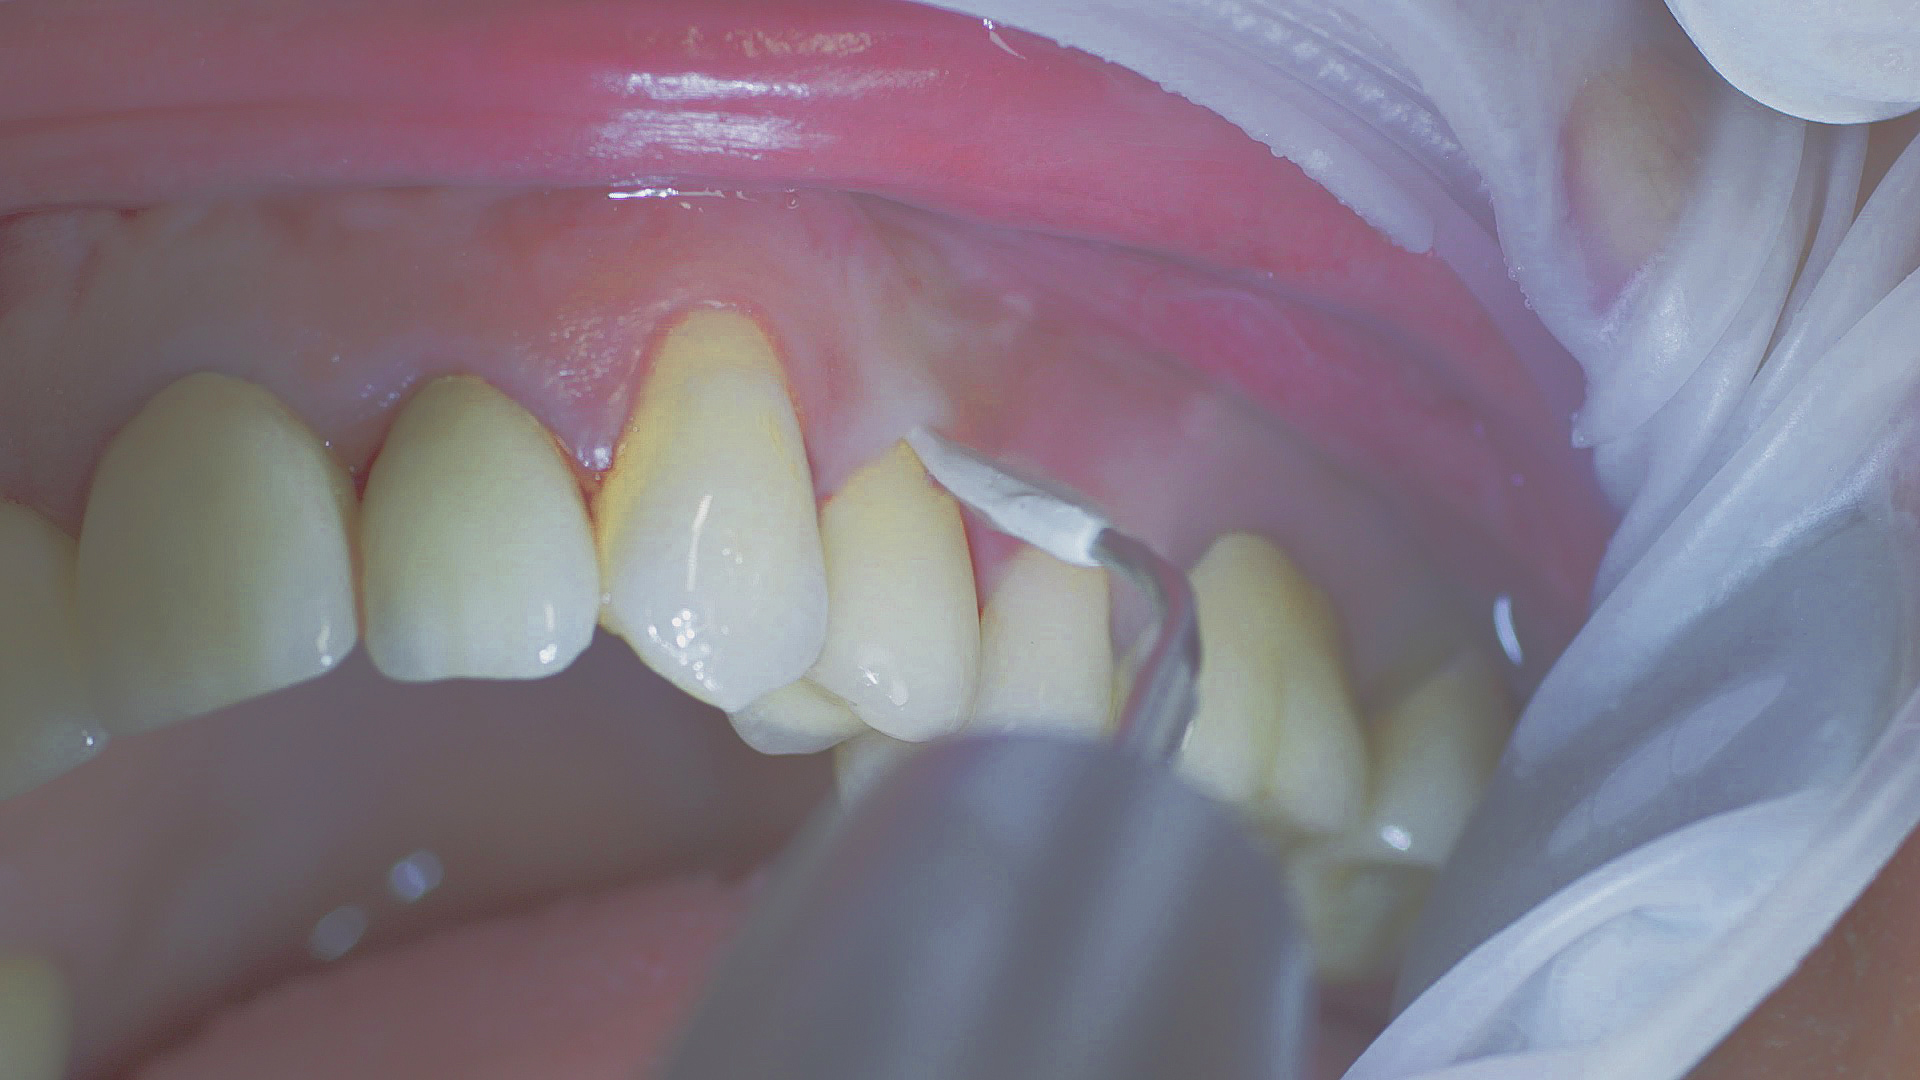

Every dental examination is based on a detailed medical history combined with targeted diagnostics con- taining as much detail as possible: The dentist records systemic risk factors such as diabetes or smoking and identifies any potential increased tendency to inflammation.[3] Hard and soft tissues are examined and periodontal pockets are probed in a screening test according to PSR (Periodontal Screening and Recording). In case of abnormal findings, the periodontal status is then re- corded and therapy is initiated where necessary. This treatment begins with professional biofilm management, by using, for example, rotary cups and polishing com pounds (Fig. 1), and comprehensive instructions in oral hygiene. Sonic or ultrasonic systems remain an effective alternative or supplement to manual instruments for sub- gingival debridement and biofilm management (presentation by Prof. Dr Ulrich Schlagenhauf;